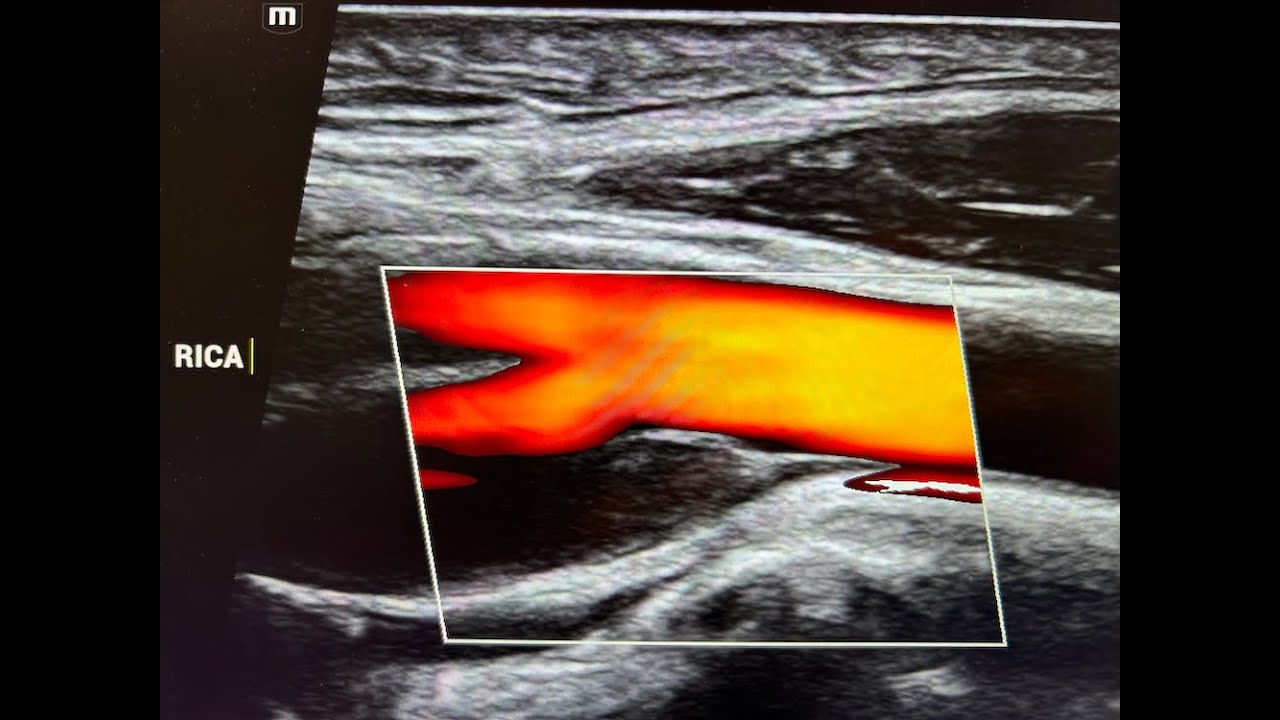

Описание: The CIMT Test, or carotid intima-media thickness test, from CardioRisk Laboratories is a favorite exam at our practice. Zachary Lott, NP discusses the reasons why he favors this test and how it compares to the coronary artery calcium score and carotid duplex. The CIMT test is a tool that can be used for initial screening for cardiovascular disease and for annual monitoring for arterial health.

Zachary Lott, NP - The CIMT Test by CardioRisk Laboratories, and why it's my favorite.